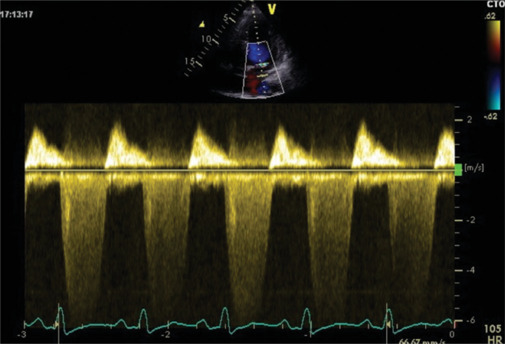

Patent foramen ovale (PFO) is a congenital cardiac defect present in approximately 30% of the general population. While often asymptomatic, it is associated with cryptogenic stroke and paradoxical embolism. Percutaneous closure using atrial septal defect occluder is an effective preventive strategy, but these devices carry a risk of rare complications, including infective endocarditis. Device-associated infective endocarditis is often linked to transient bacteremia following invasive procedures, highlighting the importance of antibiotic prophylaxis. However, the clinical presentation can be variable, requiring a high index of suspicion and advanced imaging for the diagnosis. We describe the case of a 55-year-old woman with hypertension, obesity, and a history of PFO closure with an Amplatzer occluder, who developed infective endocarditis weeks after a dental procedure. She presented with fever, vomiting, and confusion, initially misdiagnosed with encephalitis. Transesophageal echocardiography revealed large filamentous vegetation on the Amplatzer occluder, causing functional mitral regurgitation. Blood cultures identified Staphylococcus aureus and Streptococcus pneumoniae, confirming a mixed bacterial infection. The patient underwent surgical removal of the infected device and mitral valve repair. Postoperatively, she improved significantly and was discharged with a complete course of antibiotics. This case underscores the need for vigilance in patients with intracardiac devices, particularly following bacteremia-inducing procedures. Early diagnosis using echocardiography and prompt surgical intervention are essential to managing device-related infective endocarditis. While antibiotic prophylaxis may reduce the risk of bacteremia-related infections, the lack of high-quality evidence necessitates further research to guide preventive strategies. Multidisciplinary care and strict adherence to diagnostic and therapeutic protocols remain pivotal to improving patient outcomes.